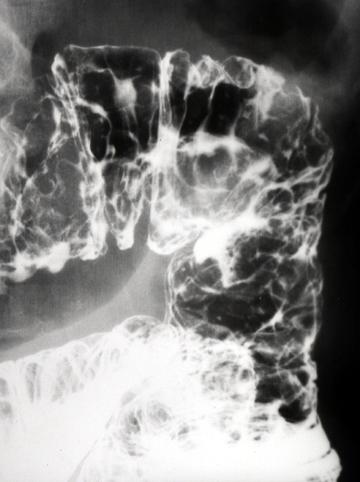

A case of malignant lymphoma which mainly involved the small intestine with multiple polypoid lesions.

Malignant Lymphoma/Malignant lymphoma

Duodenum/More than one of above

X-ray